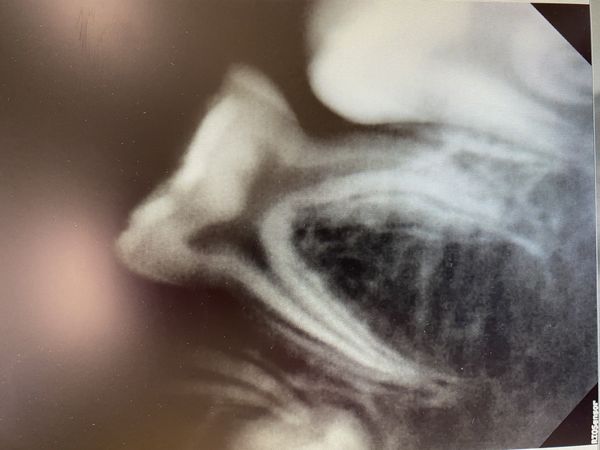

По результатам прицельного снимка, кариес сообщался с пульповой камерой. Под молочным зубом не было зачатка постоянного зуба.

- сделали рентген-снимок, который показал, что каналы были запломбированы на всём протяжении до верхнего отверстия, изменений в тканях, окружающих верхушку зуба, не было;